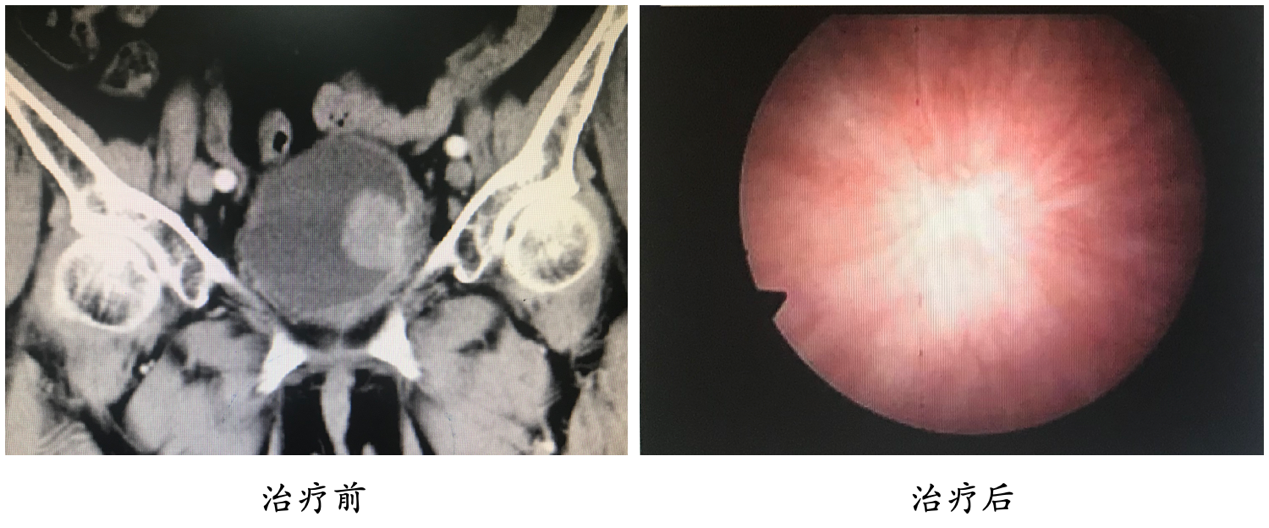

面对膀胱癌的高发病率、高恶性度以及高死亡率,为使中国膀胱癌患者获得更为先进以及更优化的膀胱癌治疗手段,北京大学第三医院成立了膀胱癌多学科诊疗团队(multidisciplinary therapy, MDT),以综合治疗为手段,提高膀胱癌患者的整体治疗效果和治疗后的生活质量。以此为契机,膀胱癌MDT团队已经开展了多项保留膀胱治疗项目,并申请了国际临床试验(NCT03756207),将国际先进的治疗方案引入国内,并且结合临床经验,不断改进和更新,为中国膀胱癌患者提供更优化的治疗方案。经过不断的治疗努力,已经有一批患者在我院接受了保留膀胱治疗,并且效果良好。

图3:典型病例介绍